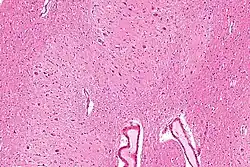

The dentate nucleus refer to a pair of deep cerebellar nuclei deep within the white matter of the cerebellum of the brain with a dentate – tooth-like or serrated – edge. The dentate forms the largest pathway between the cerebellum and the remainder of the brain.[1] It is the largest and most lateral of the four pairs of deep cerebellar nuclei, the others being the globose and emboliform nuclei, which together are referred to as the interposed nucleus, and the fastigial nucleus.

The dentate nucleus is highly convoluted, with gyri (ridges on the cerebral cortex) and sulci (furrows or grooves on the cerebral cortex). Its formation is coincident with a critical period of extensive growth in the fetal dentate. The dentate nucleus becomes visible in the cerebellar white matter as early as 11–12 weeks of gestation, containing only smooth lateral (towards the side(s) or away from the midline) and medial (towards the midline) surfaces. During this time, the neurons of the dentate nucleus are similar in shape and form, being mainly bipolar cells.[2]

During 22–28 weeks of gestation, which is the critical period in fetal development of the dentate nucleus, gyral formation occurs extensively over the entire surface.[3] Here, neurons mature into various forms of multipolar cells,[3] and the most frequent neuronal types are medium-sized to large neurons.[2]

Morphology

The dentate nucleus is highly convoluted[3] and can be divided into dorsal (motor) and ventral (nonmotor) domains. The ventral half is much more developed in humans than in great apes, and it appears to play an important role in fiber connection. Further, the ventral domain mediates higher cerebellar functions, such as language and cognition, as well as versatile and coordinated finger movement.[8] While it is generally accepted that the ventral region is more recent on an evolutionary timescale, current 3-Dimensional imaging raises questions regarding this assumption, as a third axis, the rostrocaudal axis, can now be analyzed.[3] In addition, current images show that the ventral region is not physically larger than the dorsal region in humans, as would be predicted if size increases with cognitive function.[1]

The neurons of the adult dentate are divided based on size, morphology, and function into large principal and small local circuit neurons.[6]